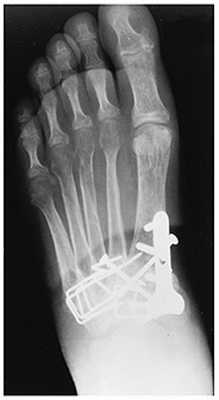

Открытое вправление вывиха, трансартикулярная фиксация 1-2-3 предплюсне-плюсневых суставов винтами.

После осмотра в отделении ортопедии №2 ГКБ №13 принято решение о проведении операции - открытому устранению вывиха, артродезе 1-2-3 плюсне-клиновидных суставов, 1 межклиновидного сустава при помощи винтов и пластины, трансартикулярной фиксации спицами 4-5 плюсне-клиновидных суставов.

Первым этапом выполняется удаление костно-хрящевых экзостозов и рубцовых тканей из области всего сустава Лисфранка. После этого дистальный отдел стопы приобретает мобильность, достаточную для восстановления нормальной анатомии. Остатки суставного хряща полностью удаляются с 1-2-3 плюсне-клиновидных суставов, 1 межклиновидного сустава при помощи долота, осцилляторной пилы, кусачек Люэра, острой ложки Фолькмана. Для репозиции используются костные цапки.

Вершиной, ключом, блокирующим клином - в общем главной частью сустава Лисфранка является 2 плюсне-клиновидный сустав. По этой причине мы предпочитаем начинать фиксацию именно с него. Для артродеза используем винты с направленной в разные стороны резьбой FT Arthrex диаметром 4 мм. Они позволяют создать мощную межфрагментарную компрессию, а за счёт глубокой резьбы очень надёжно фиксируются в кости.

После восстановления 2 луча выполняем артродез межклиновидного сустава и 1 плюсне-клиновидного сустава. Учитывая что основная нагрузка ложится на 1 луч, дополнительно стабилизируем его при помощи пластины.